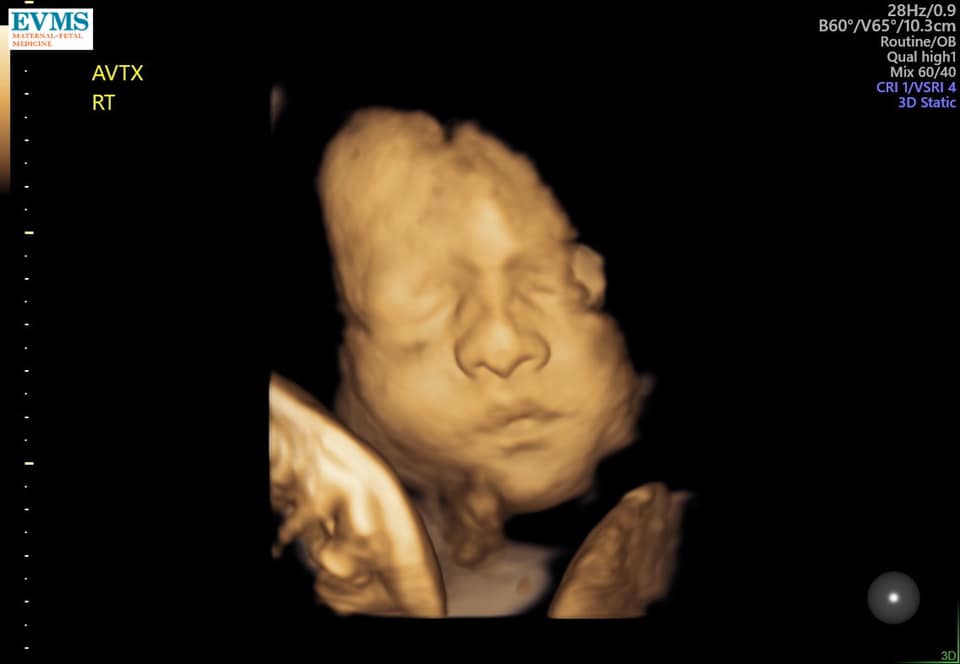

- Ultrasound Photos at 32 Weeks Pregnant With Twins

Ultrasound Photos at 32 Weeks Pregnant With Twins